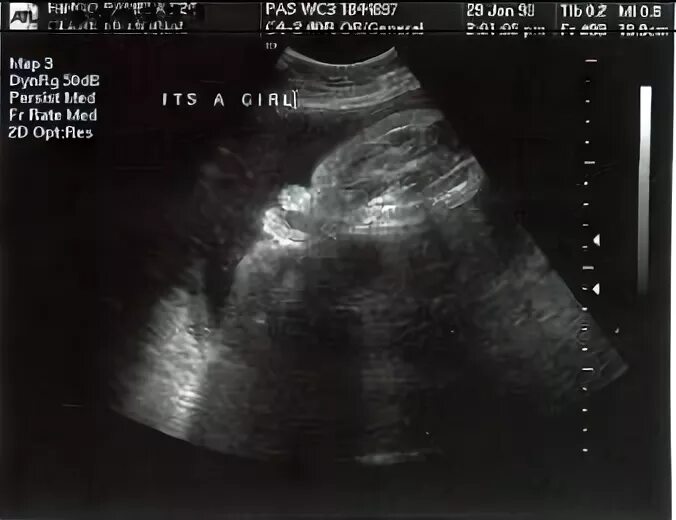

Ребенок исчез во время узи как называется